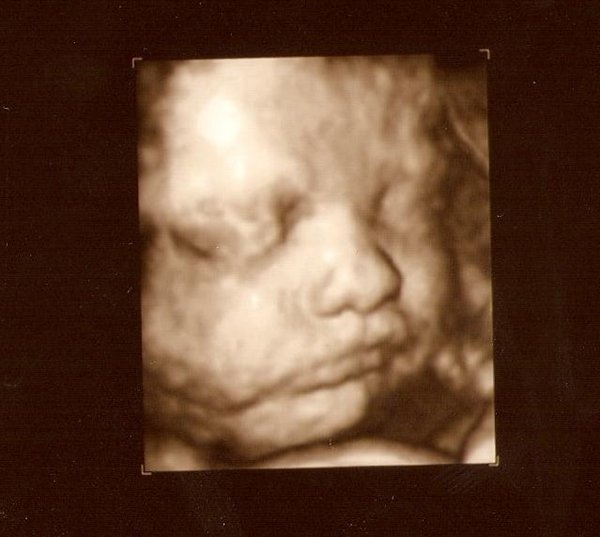

jeg tror ikke barnet er for stort efter uge 30, men det kommer måske an på hvor stor barnet er. Da jeg blev 3D/4D scannet vejede den lille ca. 1761 gram, mit lille problem var bare at vores bebse lå med hovedet godt ned allerede, så hun var nød til at scanne mig imens jeg lå på siden, for lige at få ansigtet frem

Og det er ikke så rart at ligge 45 min. på siden

Men vi fik fine billeder med hjem